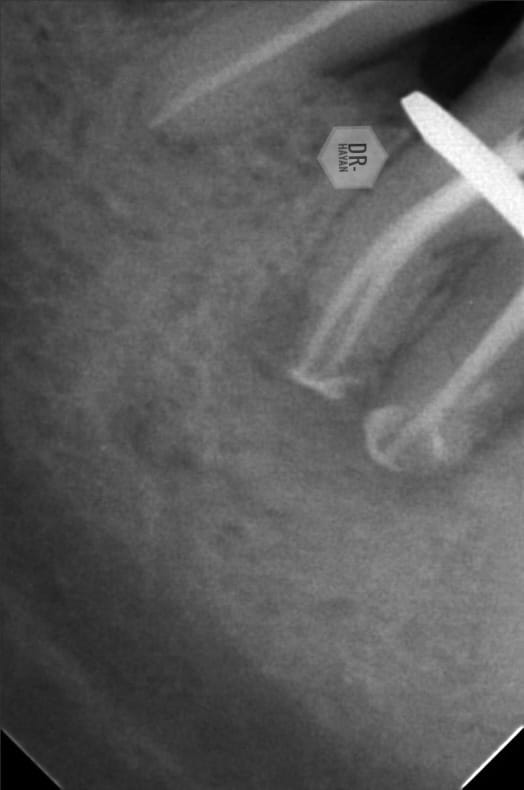

Here , you need

- Sharp explorer probe

- Ulra sonic endo tip ( diamond coated)

- good illumination

After some minutes, I found it

Deep split mb & ml canal